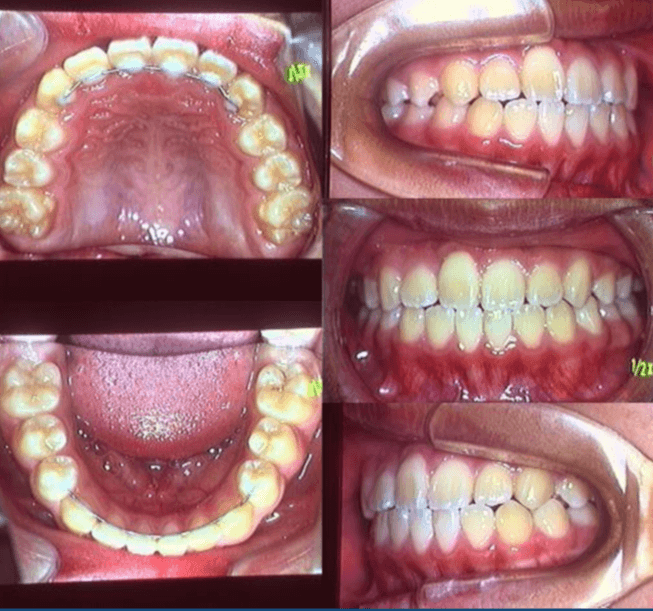

早期矯正治療 埋伏歯症例②

主訴 | 上顎前歯の位置異常に不安を抱え、歯並びと将来的な咬合状態を整える目的で来院された患者様です。 特に左側の前歯(中切歯および側切歯)の萌出が確認できないことがきっかけとなりました。 |

---|---|

診断結果 | 8歳3か月の男児。 左上1番(中切歯)と左上2番(側切歯)が埋伏し、発育方向にも異常が認められました。加えて、一部先天性欠如も確認されており、歯列全体の成長に影響を及ぼす可能性があると診断されました。 |

治療内容 |

|

治療後の経過 | 動的治療後は3〜4か月ごとの定期検診を行い、上下顎の骨の成長や第二大臼歯の萌出状況を確認しながら、本格的な矯正治療を行う |

治療期間 | 動的治療期間:約5年10か月 |

治療費用 | 460,000円(税別) |